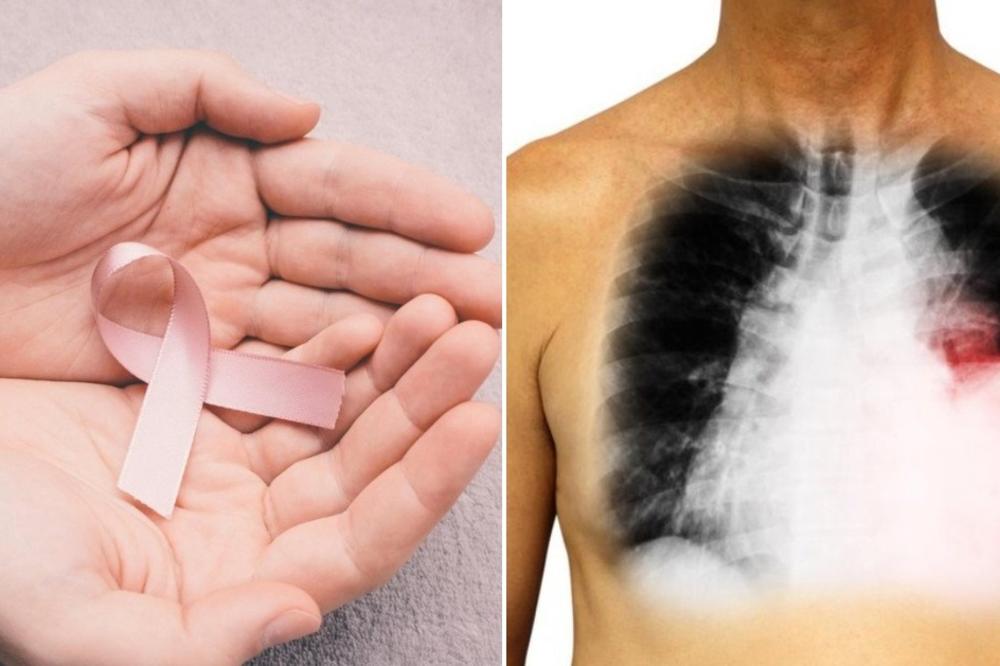

Simptomi koji ukazuju na pojavu karcinoma pluća su slični simptomima pušačkog bronhitisa, ponavljanih infekcija disajnih puteva, hroničnog opstrukcijskog bronhitisa – dakle najčešćih hroničnih stanja i bolesti disajnih organa, što upravo najčešće ometa sumnju na ovu tešku bolest, te se bolest kasno prepozna. Među najčešćim simptomima su kašalj, suv ili sa iskašljavanjem sekreta, otežano disanje i/ili osećaj nedostatka vazduha, bol u grudnom košu, promuklost. Neretko neobjašnjiv umor, ponekad iskašljavanje sukrvice ili krvi koje uvek pacijenta vodi lekaru, ili otok vrata i lica, gubitak apetita i telesne težine, bol ramenu. Treba imati na umu da su upravo kašalj sa iskašljavanjem i otežano disanje takođe uobičajeni simptomi pušačkog bronhitisa i hronične opstrukcijske bolesti pluća, pa ti pacijenti često promenu karaktera ili inteziteta kašlja ne dovode u vezu s ovom teškom bolešću. Osobe sa plućnim karcinomom ponekad imaju česte respiratorne infekcije, poput zapaljenja pluća, a poseban oprez je potreban kod pacijenata kod kojih se pneumonije javljaju u kraćem vremenskom intervalu u istom plućnom krilu. Kod trećine pacijenata koji imaju karcinom pluća, javlja se izraženi gubitak telesne mase i malaksalost. Bol u ramenu ili ruci, povremeno su simptomi, i često se dugo leče pogrešno - fizikalnom terapijom, kod reumatologa ili neurologa, dok ne postane očigledno da je reč o uznapredovalom karcinomu pluća sa urastanjem u nerve.

Pušači od svoje 50 - 55. godine, treba da idu na redovne godišnje preglede, pri čemu stručnjaci savetuju na svakih par godina i takozvani niskodozni skener pluća. Genetika, takođe, igra značajnu ulogu u nastajanju karcinoma pluća, te su u većem riziku da obole od ove bolesti osobe kojima je član porodice imao rak pluća, rak grla i bilo koje druge maligne tumore.

Šanse za uspešno izlečenje su decenijama imali samo pacijenti kojima se bolest otkrije u ranoj fazi i koji su operisani, a u poslednjih 15 godina situacija se drastično menja pojavom persolizovane ili precizne terapije, molekularne-biološke terapije i najnovije imunološke terapije.